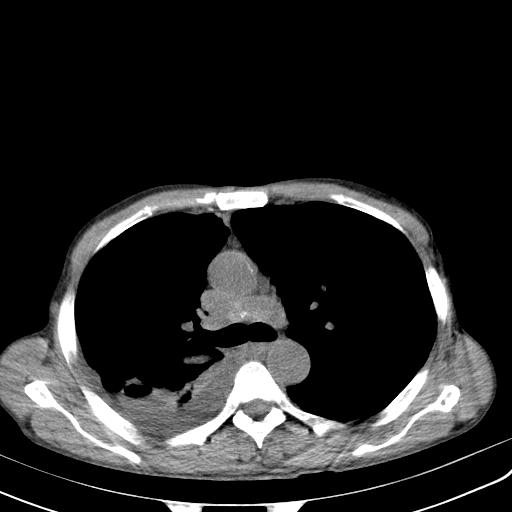

男性 75  咳嗽 一周前发热最高达39

右肺继发型tb并右侧tb性胸腔炎,右侧胸腔大量积液并右下肺膨胀不全,慢支肺气肿、多发肺大泡。建议抽胸水实验室检查并复查排除恶性在占位。

右上肺继发型肺结核,右胸腔中等量积液。

左上肺大泡。

结核的基础上有纵隔淋巴结肿大,右侧有胸水,但右侧纵隔反而窄,说明有肺有不张。

再就是右下肺有块影,和不张混合,还是不能除外肺癌。

1)右肺继发型肺结核。2)左肺胸膜下多发性肺大泡。3)右侧胸腔积液。